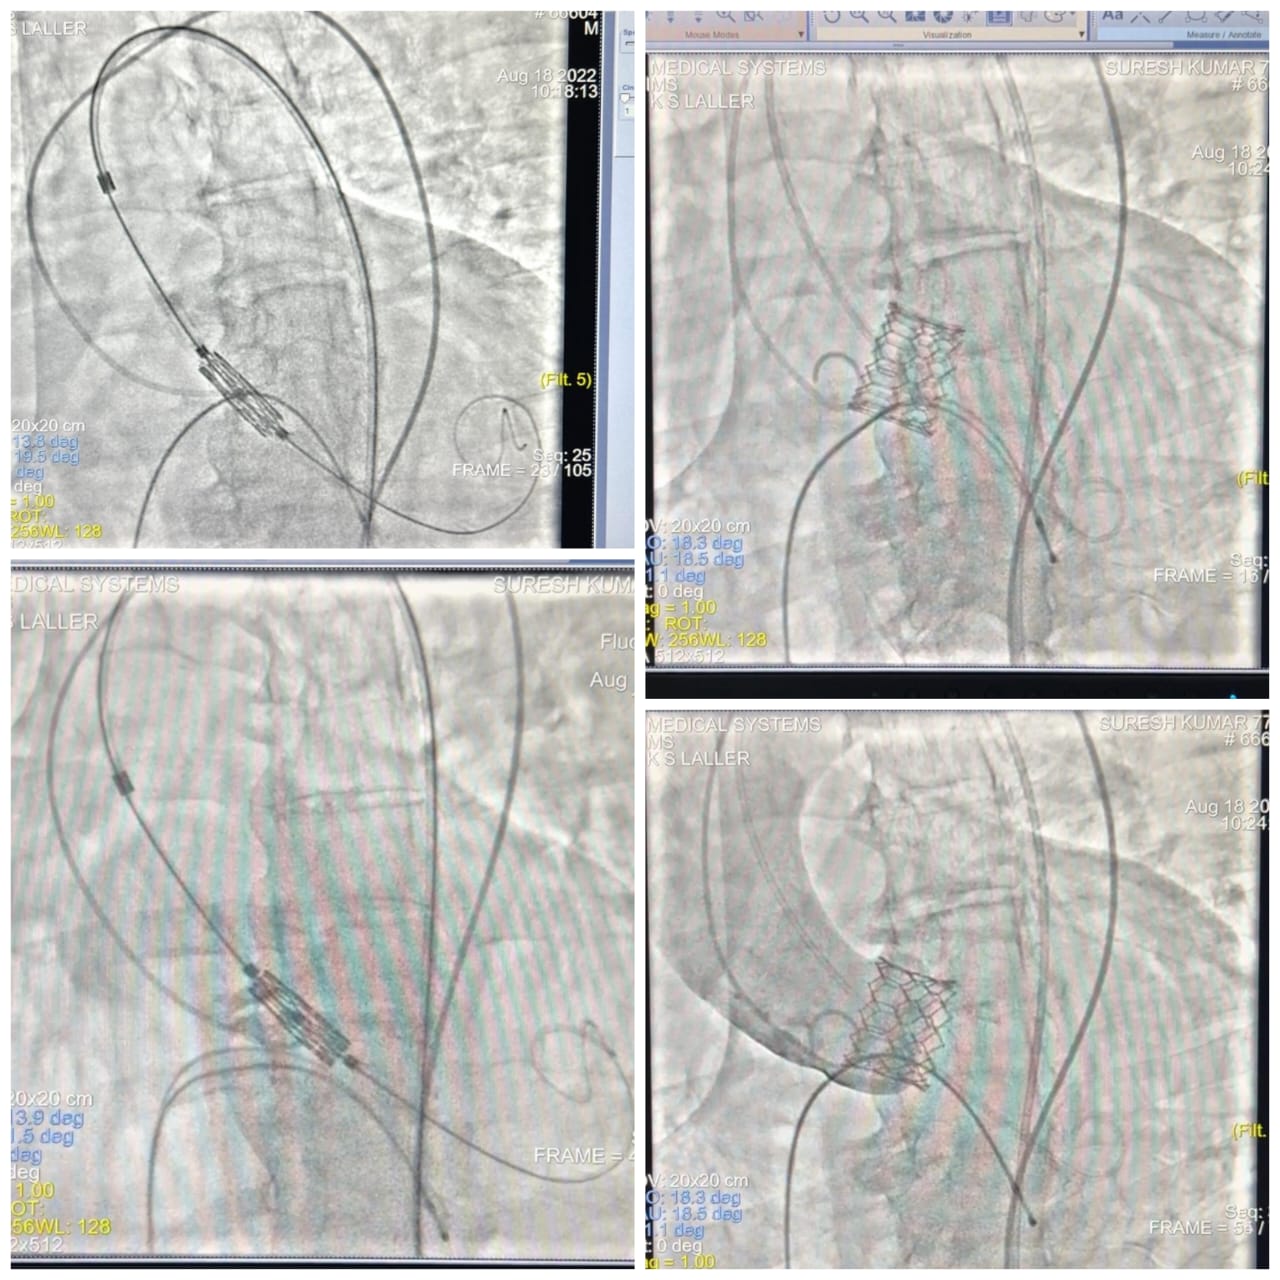

Transcatheter Aortic Valve Replacement (TAVR)

Transcatheter Aortic Valve Replacement (TAVR) is a minimally invasive procedure used to replace a narrowed aortic valve that fails to open properly—a condition known as aortic stenosis. It’s a game-changer, especially for patients who are at high or intermediate risk for open-heart surgery.

How the TAVR Procedure Works

• Access Site: A catheter is inserted through the femoral artery in the groin (or sometimes through other arteries).

• Valve Delivery: A collapsed artificial valve is advanced through the catheter to the heart.

• Deployment: Once correctly positioned, the valve expands, pushing the old valve aside.

• Function Restored: The new valve immediately takes over the job of regulating blood flow from the heart to the body.

The entire process is monitored using real-time imaging and usually takes 1–2 hours.